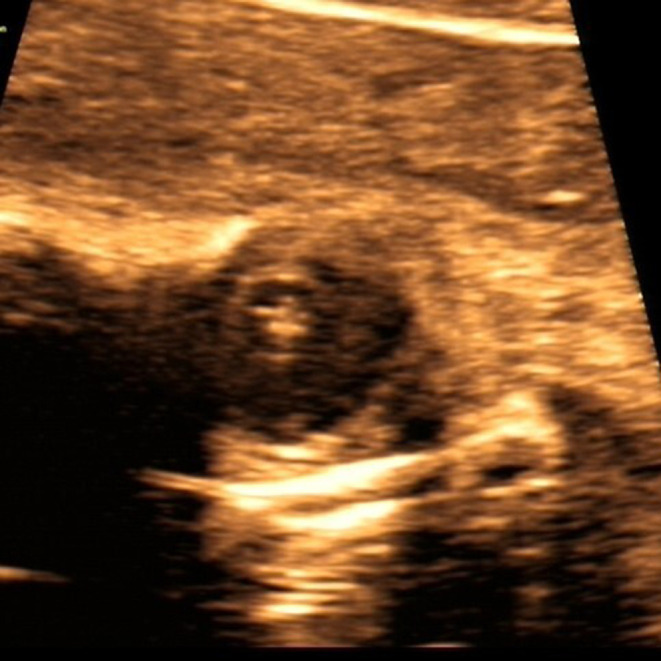

Results: Among the 29 cases, 18 (62.1%) showed complete hyperechogenicity of the lens (type I), 6 (20.7%) showed dot or cluster hyperechogenicity within the lens (type II), and 5 (17.2%) showed the "double-ring" sign (type III). Moreover 18 (62.1%) involved isolated cataract and 11 (37.9%) involved cataract associated with extraocular abnormalities, with central nervous system and cardiac abnormalities being the most common. In terms of potential etiology, five cases (17.2%) had a family history, and genetic testing was performed in eight cases, with five of them showing abnormalities. Cases 2 and 16 involved two fetuses of the same pregnant woman, both of which had a hemizygous mutation of the OCRL gene (c.1514G > A). Moreover Case 3 involved Trisomy 13, and Case 17 had heterozygous mutations of the RAB3GAP1 gene (c.718C > T and c.1879dupA). Furthermore, Case 21 had a heterozygous mutation of the NHS gene (c.375C > A). Among the 29 cases, pregnancy was terminated in 21 (72.4%) and was continued in 4 (13.8%).

Conclusion: Congenital cataract, defined as lens opacity, presents as complete hyperechogenicity of the lens, a double-ring sign, or dot and cluster hyperechogenicity within the lens on prenatal ultrasound. Prenatal ultrasound can help assess the eyes and other systems during prenatal or postnatal examinations and can provide additional information for prenatal counseling and early postnatal treatment of congenital cataract.